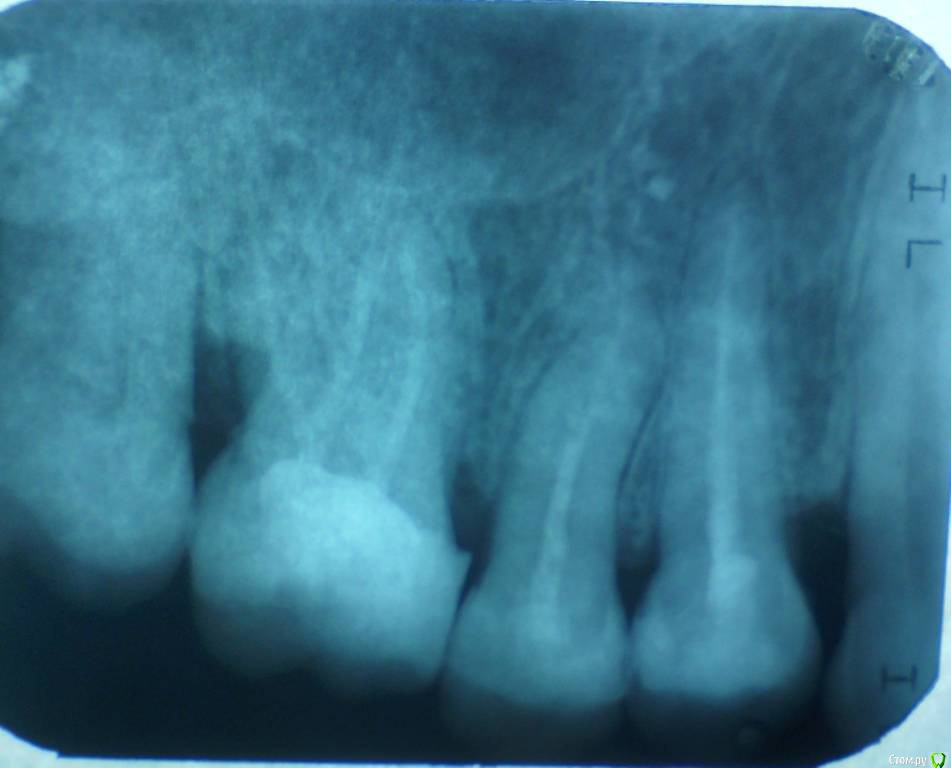

St. Опубликовано 26 августа, 2016 Поделиться Опубликовано 26 августа, 2016 Все три пролечены не очень хорошо, в идеале перелечить и сделать на них коронки. Но на сладкое ни один из них не может реагировать. Возможно реагирует 7 или 3, у которых оголена часть корней за счет вашего парадонтита. 1 Ссылка на комментарий

Гарриевич Опубликовано 27 августа, 2016 Поделиться Опубликовано 27 августа, 2016 возможно пропущенный канал, а возможно Вам "кажется" и реагируют все таки живые зубы. В любом случае данный снимок показывает не очень качественное лечение, но это только снимок 1 Ссылка на комментарий

татьяна tat Опубликовано 27 августа, 2016 Автор Поделиться Опубликовано 27 августа, 2016 возможно пропущенный канал, а возможно Вам "кажется" и реагируют все таки живые зубы. В любом случае данный снимок показывает не очень качественное лечение, но это только снимок Ссылка на комментарий

Beznika Опубликовано 8 сентября, 2016 Поделиться Опубликовано 8 сентября, 2016 на 5 ке материал вывели за апекс. резекцию возможно придётся делать верхушки корня... + карман у вас есть за 6кой. а так всё равно перелечивать надо... масса пористая в каналах и не гомогенная. (не однородная) Ссылка на комментарий